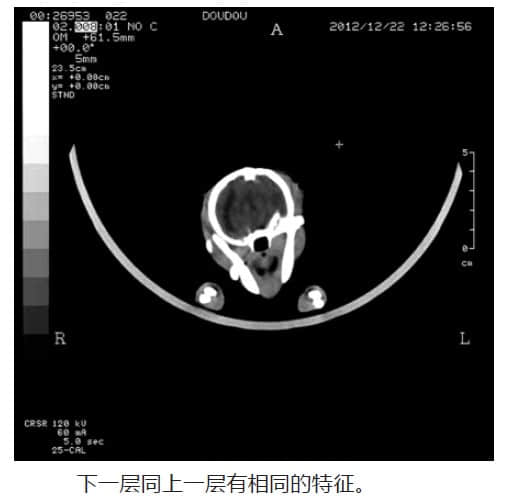

CT影像所见:颅骨三处如缺,最宽处0.9cm。双侧大脑半球对称,灰白质对比正常,未见局灶性密度异常,中线结构居中,双侧侧脑室前角、第三脑室 及四脑室对称性中度扩大,侧脑室宽1.33cm,右侧侧脑室的上角和下角通路异常增宽,幕下小脑、脑干无异常。囟门未闭合,宽0.6cm。侧脑室体部宽度 指数:3.98./2.46=1.62。

脑积水,颅内压过高引起的囟门及颅骨未闭合,激动后颅内高压引起的抽搐。右侧脑室扩张比左侧严重,怀疑导致向左侧转圈。